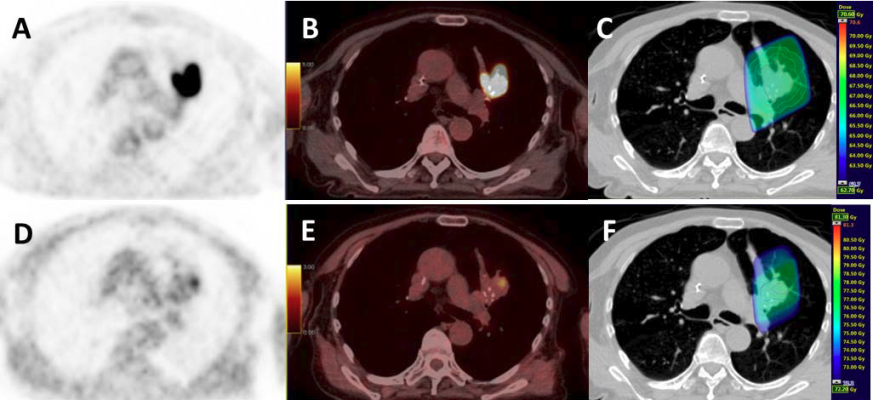

A An 81 Year Old Patient With Centrally Located Non Small Cell Lung Download Scientific Diagram